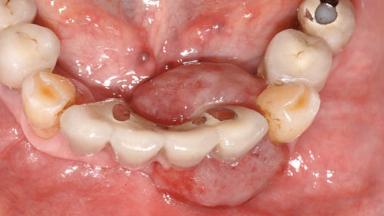

Case Type Extended Space

Jaw Mandible

Area Anterior|Posterior

# of Teeth 10

# of Implants 5

Type of Implants One-Piece

Prosthesis Type FDP